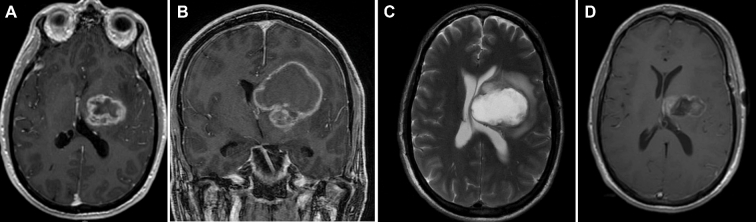

成人胶质母细胞瘤较常见于大脑半球,很少发生在间脑等深层结构。由于这些病变在很大水平上被认为是不可切除的,导致细胞减少性疾病控制较差,胶质母细胞瘤研究传统上排除了深部肿瘤患者。丘脑胶质母细胞瘤(GBMs)的治疗具有挑战性,因为它们位于大脑深处,使得它们很难根治性手术切除。管理策略从针吸活检,到部分或更的切除,甚至没有组织学确认的经验治疗。尽管较近有证据表明,空间位置可能决定胶质瘤的生物学行为,如儿童GBM和弥漫性固有脑桥胶质瘤,丘脑GBMs很少单独研究或大量研究。

虽然已知深部病变立体定向活检后会出现较高的并发症,在肿瘤水肿的背景下,丘脑与主要功能区的密切关系可导致活检或手术后的神经功能缺损。还应注意的是,这一并发症发生率(16%)可能存在有利的偏差,因为许多其他患者可能已经在其他地方接受了治疗,并出现了严重的并发症,这使得咨询到该三级护理中心的可能性较低。丘脑胶质瘤的一线治疗仍是手术。

研究发现,高级别肿瘤患者的OS为12个月,这与我们GBM队列中的发现相似。值得注意的是,本研究中的高级别肿瘤包括间变性星形细胞瘤、少突胶质细胞瘤、少突星形细胞瘤和间变性室管膜瘤,这些肿瘤的OS优于GBM。此外,据报道围手术期死亡率为4.5%,约一半的患者出现短暂性偏瘫。其他并发症,如感觉和视觉退化,分别发生在15.1%和5.7%,除了脑水肿和语言退化,这并不少见。Sai Kiran等人报告12例丘脑基底神经节瘤患者接受了的切除术。超过一半的患者实现了近全切除。Steiger等人报告14例丘脑星形细胞瘤,其中较大限度的显微手术切除。3例为GBMs,1例术后出现视力障碍。1例患者术后4个月死亡,其余2例随访时间分别为6个月和10个月。这些研究的结果表明,考虑到疾病的侵袭性和辅助治疗开始前康复的有限时间,丘脑胶质母细胞瘤的侵袭性切除可能是有问题的。外科技术的未来进展,加上术中神经生理监测,可能会好转丘脑外科干预的风险状况,尽管该区域的功能和解剖位置仍将是固有的挑战。激光间质热消融术(litt)是目前临床试验的一个主题,是立体定向活检后可以进行的另一种选择,应予以考虑。